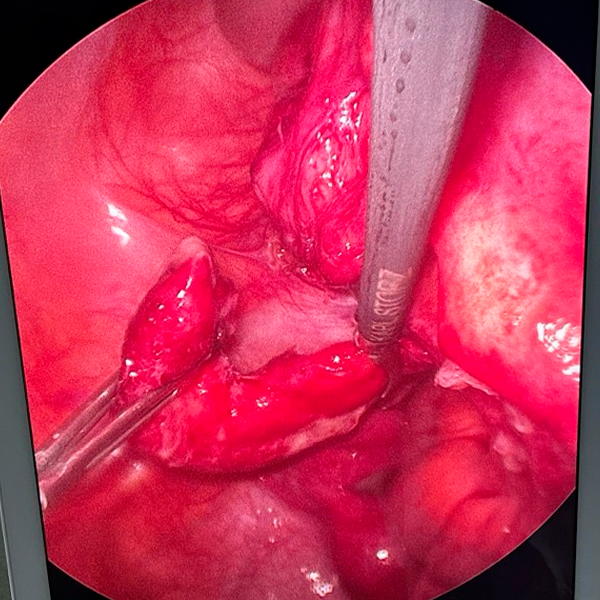

3. Visualización:

La cámara transmite imágenes del interior del abdomen a un monitor, permitiendo al cirujano visualizar el apéndice y el área circundante.

4. Extirpación del apéndice:

El apéndice se separa de los tejidos circundantes y se extrae a través de una de las incisiones, a menudo utilizando una bolsa especial.